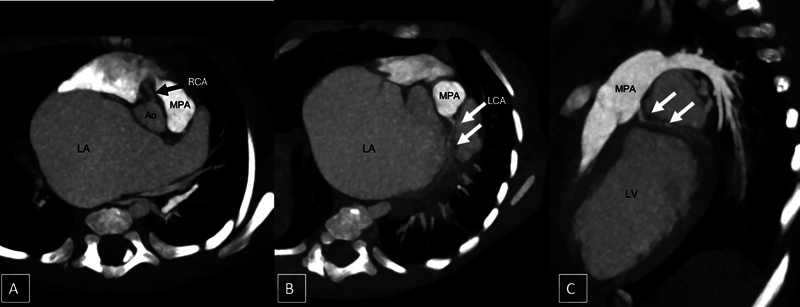

摘要左冠状动脉异常起源于肺动脉是一种罕见的先天性异常,伴有冠状动脉偷取和心肌缺血。左心室扩张导致二尖瓣反流导致左房增大。我们报告一个罕见的病例巨大左心房的婴儿与alcapa介导的继发性二尖瓣反流,这是迄今为止尚未报道。

Anomalous origin of the left coronary artery (ALCAPA) from the pulmonary artery is a rare congenital anomaly with coronary steal and myocardial ischemia. The left ventricular dilatation leads to mitral regurgitation causing left atrial enlargement. We report a rare case of giant left atrium in an infant with ALCAPA-mediated secondary mitral regurgitation, which has been hitherto unreported.